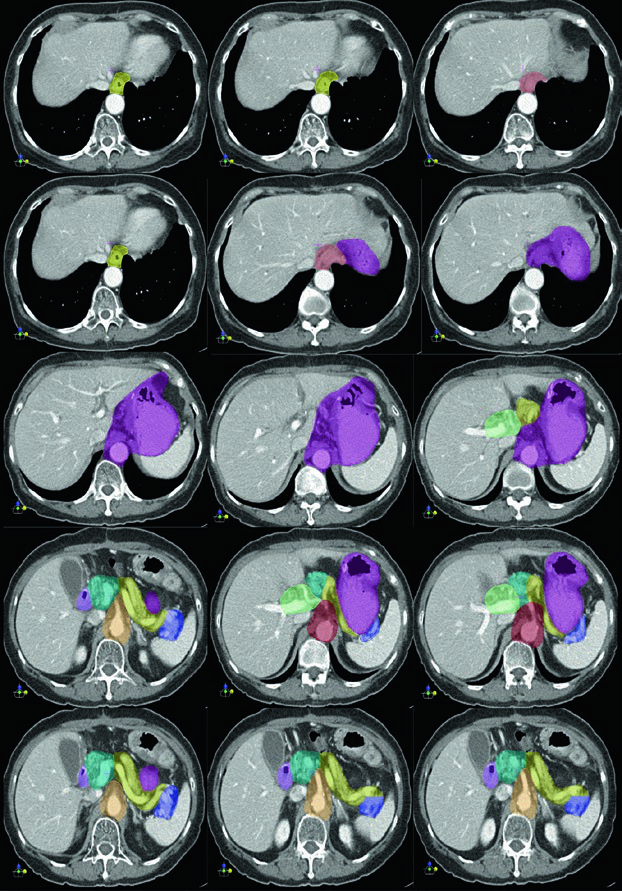

Deve-se considerar estudo de perfusão renal quantitativa bilateral antes da radioterapia, pois a função renal pode limitar o planejamento. A TC pós-operatória com contraste oral e intravenoso é obrigatória, com identificação precisa do esôfago e remanescente gástrico, da anastomose (gastrojejunal ou esofagojejunal), do coto duodenal, da porta hepática, do hilo esplênico, do pâncreas, e da artéria celíaca e artéria mesentérica superior.

Imobilização com saco a vácuo tipo VacLok é recomendada para tratamento com IMRT. Contraste intravenoso é preferido para demonstrar os vasos sanguíneos e guiar o delineamento do CTV, particularmente para as cadeias linfonodais.

Três áreas devem ser identificadas como CTV na radioterapia adjuvante: o leito tumoral gástrico, a anastomose ou cotos, e as cadeias linfáticas regionais. Além disso, o ligamento hepatogástrico deve preferencialmente ser tratado em todos os casos, pois está em alto risco de recorrência — representa a parte do omento menor que conecta a pequena curvatura ao fígado e contém os linfonodos gástricos esquerdos e direitos que nem sempre são completamente removidos na cirurgia.

Os benefícios da IMRT na radioterapia gástrica adjuvante têm sido demonstrados em diversas publicações. Quando utilizada, tanto o leito tumoral quanto os volumes subclínicos (incluindo regiões de drenagem linfática) devem ser delineados individualmente. O PTV é gerado expandindo o CTV com margem de pelo menos 1 cm, considerando movimento de órgão e incertezas de posicionamento.